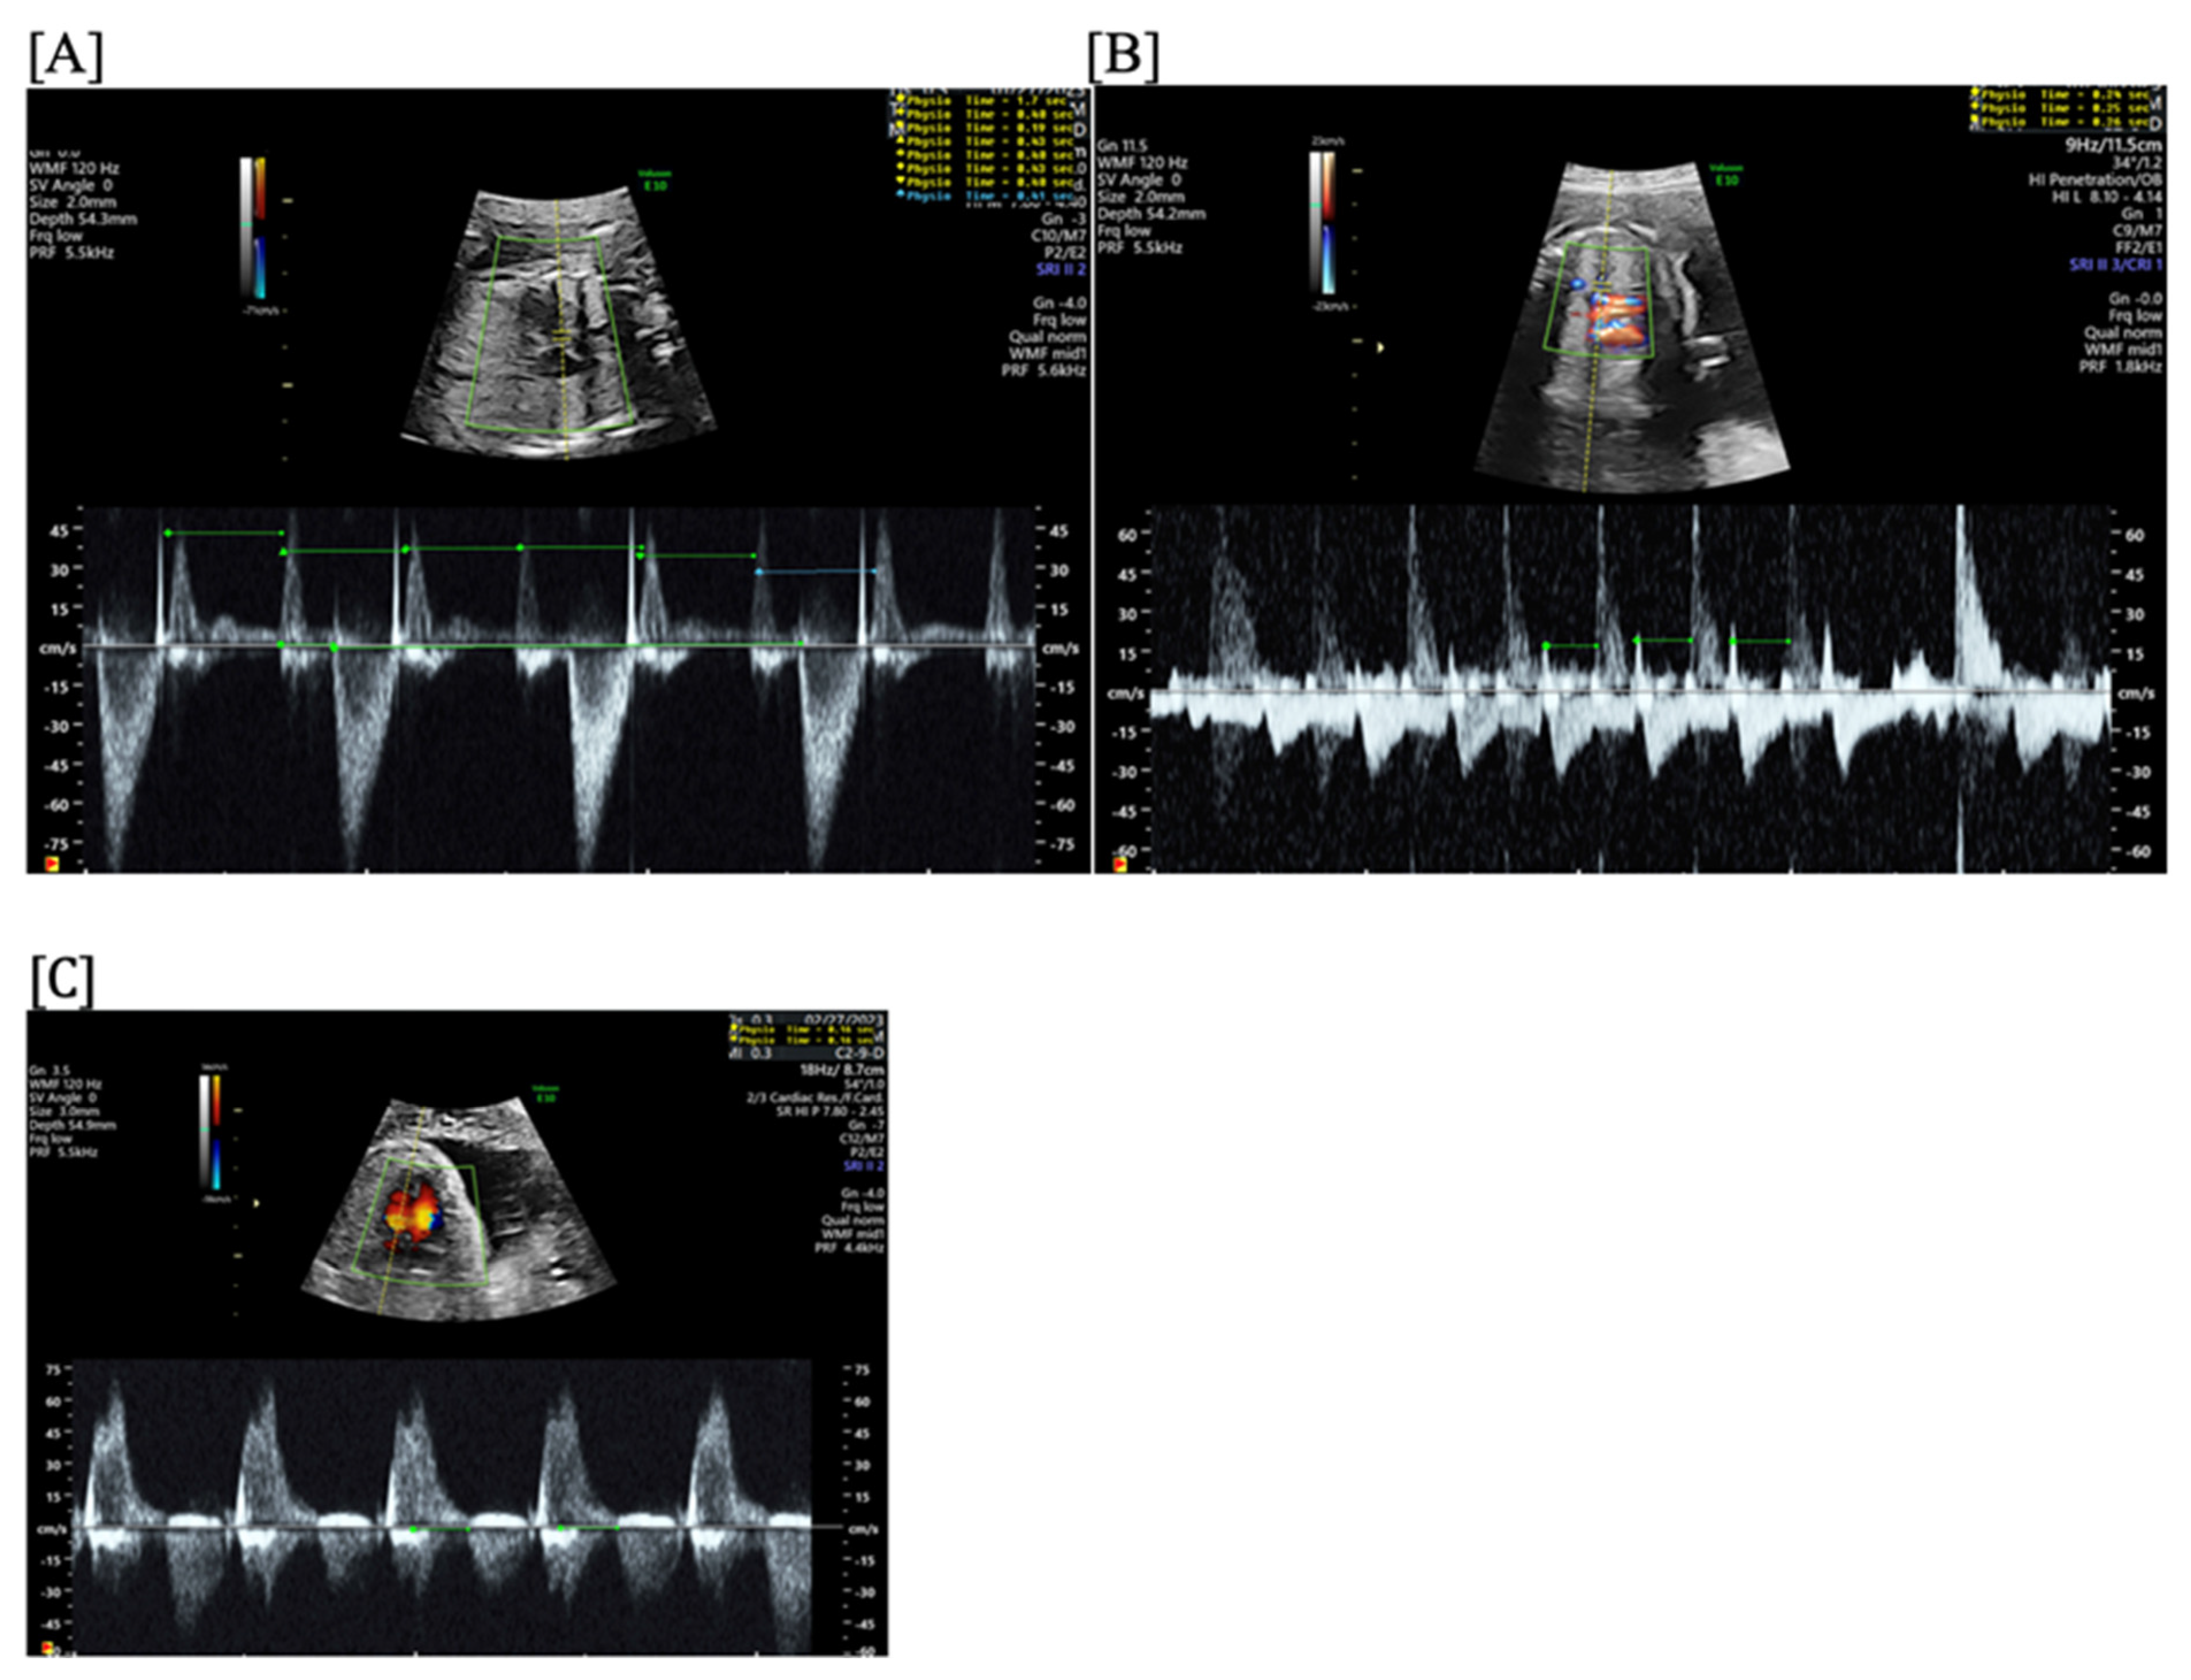

- Short VA SVT (Figure 3 and Figure 4) demonstrates a ventricular–atrial (VA) interval that is less than half of the ventricular–ventricular (VV) interval (VA:AV ratio < 1) and a sudden onset and termination of tachycardia; tachycardia usually terminates with a non-conducted atrial contraction. Short VA SVT includes AVRT (also known as orthodromic reciprocating tachycardia, ORT) and atrioventricular nodal reentrant tachycardia (AVNRT). Short VA SVT typically presents after 18 weeks of gestation.

- Long VA SVT (Figure 4) demonstrates a VA interval that is more than half of the VV interval (VA:AV ratio > 1). Long VA SVT includes EAT and PJRT. A distinguishing feature of EAT is tachycardia termination with ventricular contraction. Long VA SVT may occur as early as 12 weeks of gestation. Because long VA tachycardias have slower rates, they are less likely to cause hydrops.